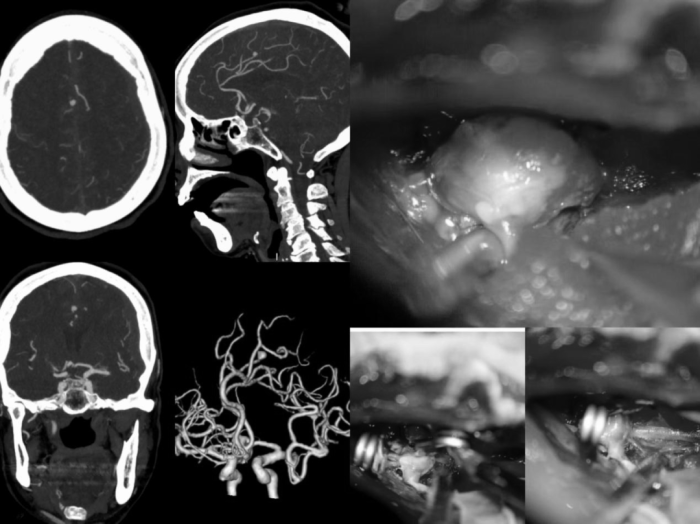

近期,72岁高龄的黄奶奶(化名),突发意识障碍紧急入院,确诊为右侧大脑前动脉动脉瘤破裂伴蛛网膜下腔出血,同时合并左侧额颞顶硬膜下血肿,双重颅内病变叠加,病情极其危重。更棘手的是,黄奶奶本身患有严重心脏瓣膜疾病、慢性心力衰竭,基础状况极差,手术麻醉风险、术后管理难度均达到临床极高危级别,救治挑战巨大......

神经外科团队凭借扎实的专业功底、成熟的手术经验,精心设计最优手术方案,果断为患者实施高难度开颅手术。术中精准定位、精细操作,一次手术同步完成动脉瘤夹闭与硬膜下血肿清除,一次性解决两大致命问题,彻底清除颅内所有隐患,手术成功。